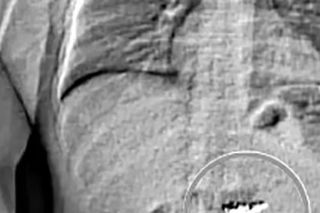

Jak przyznali policjanci w raporcie z zatrzymania, 32-latek miał powiedzieć w samochodzie: „Powinienem był wyrzucić je przez okno”. - „Czy zostanę oskarżony o to, co mam w żołądku?” - miał z kolei zapytać personel więzienia w hrabstwie Washington, co zaalarmowało śledczych. Gilder trafił do szpitala i na prześwietlenie, które potwierdziło obecność obcych ciał w jego żołądku.

Na potwierdzenie przypuszczeń, że to skradzione kolczyki, mundurowym przyszło poczekać aż dwa tygodnie. 32-latek wydalił je z organizmu w odstępie kilku dni, będąc pod opieką lekarzy i obstawą policji w szpitalu. Analiza numerów seryjnych potwierdziła, że do błyskotki z salonu Tiffany’ego. Gilder trafił do więzienia hrabstwa Orange, gdzie czeka na proces za napad i kradzież pierwszego stopnia.